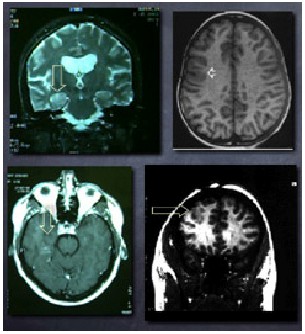

MRI and CT Scans: These are imaging methods that don't involve invasion and that show the brain in different aspects, enabling the determination of the presence of an abnormal structure that is capable of producing seizures.